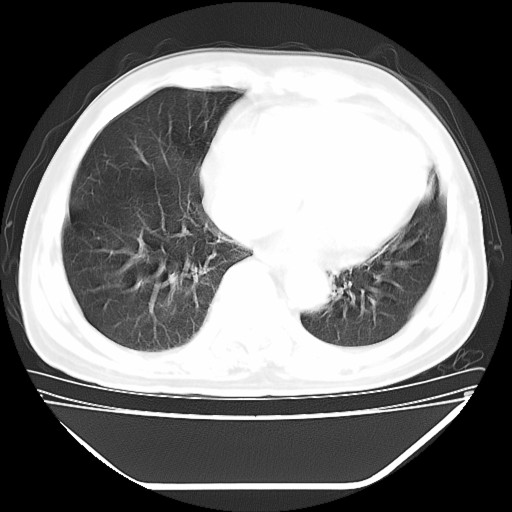

以下是引用hhcckk在2009-5-29 10:34:00的发言:[br]左下肺片絮状边缘模糊影,考虑感染,建议治疗后复查[br]